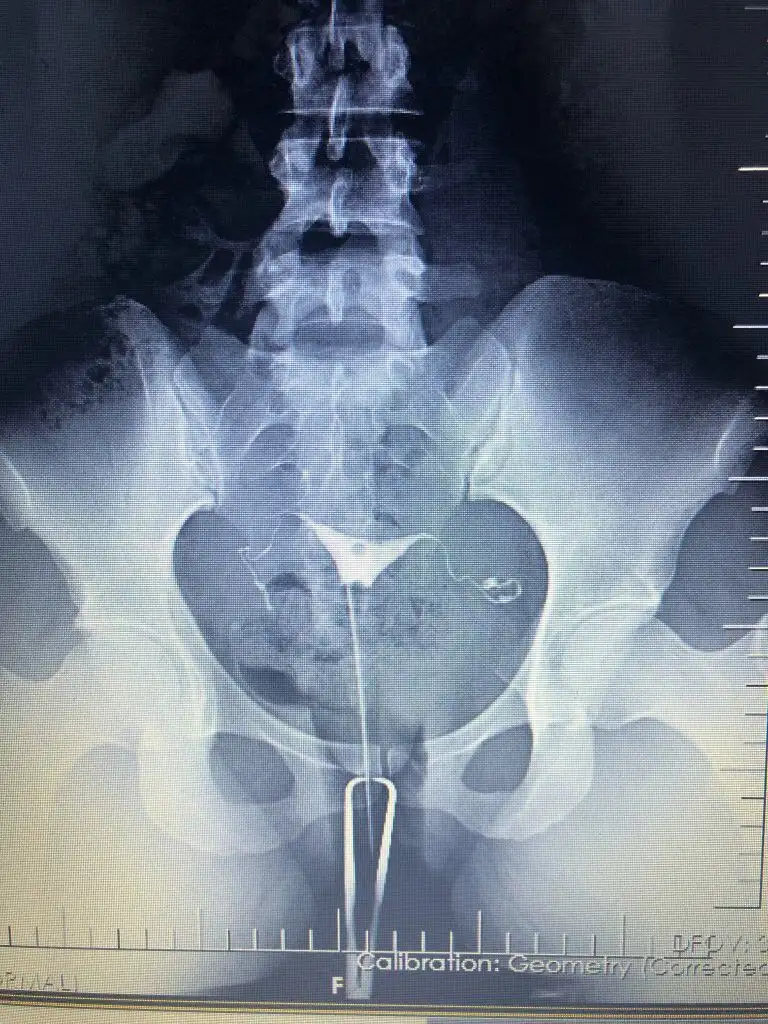

Cok teşekkür ederim.Nasil atabilirim bir bakayim cd de aldim görüntüyü yarin bilgisayardan atmayi deneyeyim bir. Kuşku birakan nedir nededi doktor.ben iki farkli doktora gittim ikiside ayni yorumu yapti. Sıvı dolu olan tüp bosaltilsa bile tekrarlama riski yüksek yani bu demek oluyor ki bosaltilr tüpü denedik bebek yapmayı olmadi herşey basa saracak tekrar hsg cekilecek kapandi mi diye gibi. Bu nedenle sıvı dolu tüpün alınması ortak karardi. Diğer tıkalı olan tüp ise hsg cekilirken doktorum zaten acmaya calismisti açılmamışti ameliyat sırasında da ilk oncelik onu açmaya calismak oldu ama geride bir dermoid kist (ameliyat sırasında görülebildi) tüpü tikamis ve acmays çalıştiklarinda tüpe basinc nedeniyle zarar vermis oyuzden oda alındı.İyi dileklerim sizinle

Özelden hsg görüntünüzü bana atar mısınız sakıncası yoksa ben iki kere çekildim normal raporlandı ama bir doktor aklımda kuşku bıraktıbu yüzden araştırma içine girdim, iki aşılamam negatif oldu

Ben Funda hanıma görselleri attığımda problem olduğunu düşünmüyorum dedi, ben çok fazla doktora gittim Çünkü bir neden bulunamıyordu yalnızca biri hidroselpenks dedi ve laparoskopi önerdi ben de o an çok şaşırıp çıktım. O yüzden bu durumu yaşayanlara mutlaka soruyorumCok teşekkür ederim.Nasil atabilirim bir bakayim cd de aldim görüntüyü yarin bilgisayardan atmayi deneyeyim bir. Kuşku birakan nedir nededi doktor.ben iki farkli doktora gittim ikiside ayni yorumu yapti. Sıvı dolu olan tüp bosaltilsa bile tekrarlama riski yüksek yani bu demek oluyor ki bosaltilr tüpü denedik bebek yapmayı olmadi herşey basa saracak tekrar hsg cekilecek kapandi mi diye gibi. Bu nedenle sıvı dolu tüpün alınması ortak karardi. Diğer tıkalı olan tüp ise hsg cekilirken doktorum zaten acmaya calismisti açılmamışti ameliyat sırasında da ilk oncelik onu açmaya calismak oldu ama geride bir dermoid kist (ameliyat sırasında görülebildi) tüpü tikamis ve acmays çalıştiklarinda tüpe basinc nedeniyle zarar vermis oyuzden oda alındı.

Benimkine hic benzemiyorBen Funda hanıma görselleri attığımda problem olduğunu düşünmüyorum dedi, ben çok fazla doktora gittim Çünkü bir neden bulunamıyordu yalnızca biri hidroselpenks dedi ve laparoskopi önerdi ben de o an çok şaşırıp çıktım. O yüzden bu durumu yaşayanlara mutlaka soruyorum

Ben İzmir’de değilim ama bir ayağım İzmir’de bu yüzden medikal aklımda olan bir yerdi buna istinaden kendisi ile yazıştım.Benimkine hic benzemiyorhidrosalpkinks diyen hangi doktor. Benim hsg cekimini yapan doktor Mehmet Bal ameliyatimida o yapti. Ama Funda hocaya hsg filmlerini göstermiş , Funda hanima o yolendirdi beni zaten. Ben bir de Engin Sarıca' ya gittim hsg raporumu götürdüm inceledi oda ayni yorumda bulundu

Yani acikcasi benimkini hatırladığım kadariyla ve simdi google dan baktığım diger örnek hidrosalpkinksler gibi degil görüntün yani bende boyle şiş bir yer gorunuyordu resmen. Hsg cekilirken ağrın oluyor mu ? Mesel ben tupleri acik olanlarda cok agrisi oluyor diye duymadim. Ben agridan mahvolmuştm ki anestezili cekilmeme rağmen. Bence normal gibi görünüyor tüplerin ama güvendiğin bir doktor varsa ve sartlaro cekimi iyi olan bir yer agrinda olmuyorsa için rahat etsin diye tekrar cektirebilirsin. Ama bence hic gerek yok bir kaç doktor ayni yorumu yaptiysa eğerBen İzmir’de değilim ama bir ayağım İzmir’de bu yüzden medikal aklımda olan bir yerdi buna istinaden kendisi ile yazıştım.